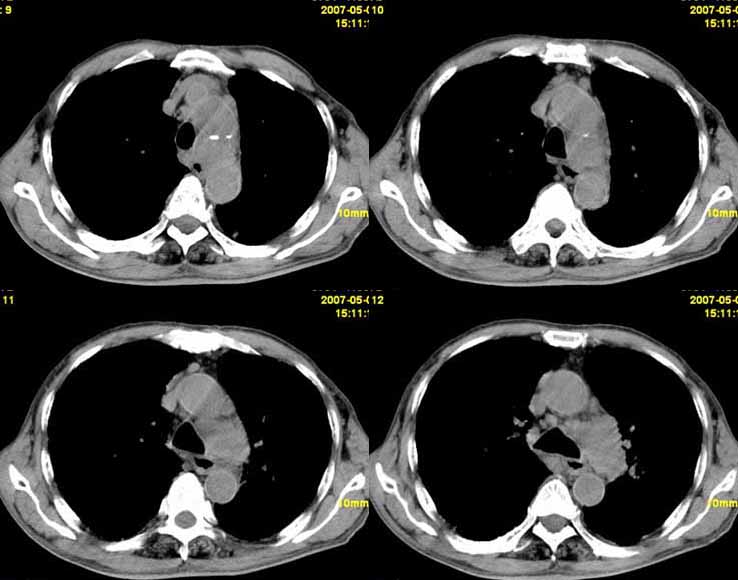

以下是引用小初学者在2007-5-12 11:09:00的发言:[br][br]双肺弥漫性质纤维化(考虑矽肺所致),并发左肺下叶背段周围性肺癌纵隔淋巴转移。

以下是引用zhangzhongshou在2007-5-12 12:09:00的发言:[br]1、左下叶背段周围型肺癌左肺门及纵隔淋巴结转移可能性大。[br]2、弥漫性肺气肿(双侧)。[br]3、双肺间质纤维化。

以下是引用老爱克斯新网客在2007-5-12 12:54:00的发言:[br]1周围型肺癌纵隔肺门淋巴结转移,2肺间质纤维化,